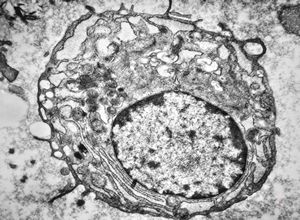

bone marrow - crystalloid inclusions Charcot-Leyden crystals formation

bone marrow - crystalloid inclusions Charcot-Leyden crystals formation v.s.